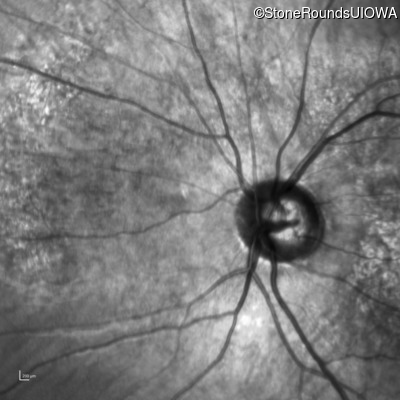

Infrared Fundus Photograph - Left - 10/160 -1

Exemplar